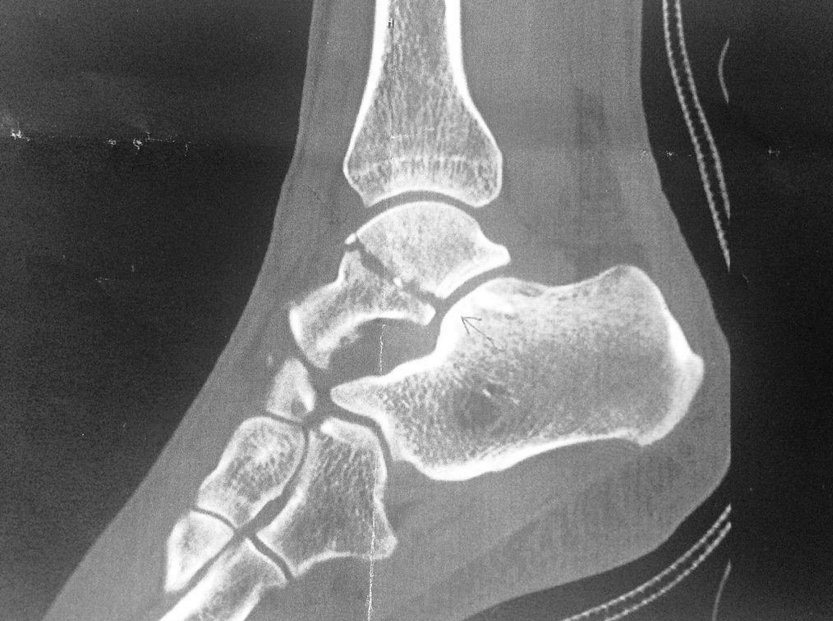

We spoke to UK rider Hannah Barnes at the Canyon//SRAM training camp where she’s meeting her team mates for the 2016 season. Whilst racing for UnitedHealthcare Pro Cycling in August she suffered a crash which resulted in a break to the talus – a complicated anklebone that has three ankle joints attached to it. Still off the bike four months later, she’s doing an incredible job at staying positive, and we wanted to find out what’s keeping her smile so bright…

Hannah looks exactly as she did last time I saw her. Still tiny, with the same impressive quad and calf muscles and the same bright and infectious smile. Yet the ‘injury boot’ hasn’t been removed and she’s still on crutches – a shock since I’d thought she’d be back on the bike by now. We both did: “I had the results from the CT scan and they said it’s not ready” she explains, “it’s healing, and it’s healing well – but it’s just slow. They said it needed another five weeks to be 100 per cent better.”

Hannah's x-ray image